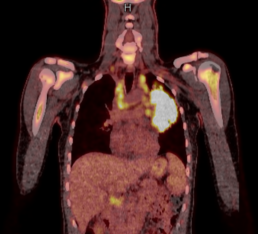

Die Strahlentherapie ist neben chirurgischen Optionen und systemischer Chemotherapie eine sehr wichtige Komponente der Krebstherapie. Viele Tumoren sind mit interdisziplinärer Zusammenarbeit in Tumorboards und entsprechenden Therapiekonzepten heilbar. Fortgeschrittene Tumorstadien mit Metastasen erfordern eine schmerzreduzierende strahlentherapeutische Behandlung. Holen Sie sich eine zweite Meinung für die primäre Strahlentherapie und Nachbestrahlungen bei allen Krebsarten.

Strahlentherapie der geeigneten Tumorentitenten/Tumormetastasen und der gutartigen Erkrankungen

Die Strahlentherapie ist neben chirurgischer Option und systemischer Chemotherapie sehr wichtige Komponente der Krebstherapie. Viele Tumoren sind mit interdisziplinärer Kooperation am Tumorboards und passenden Therapiekonzepten heilbar. Die fortgeschrittene Tumorstadien mit Metastasen benötigen schmerzreduktiven strahlentherapeutischen Tretman. Holen Sie sich eine zweite Meinung für primäre Strahlung und Nachbestralungen aller Krebsarten.

Tumornachsorge/Nachkontrolle

Nach Beendigung einer Radiotherapie werden , um eventuelle symptomatische

Therapie zu optimieren und Therapie-Response zu checken, üblich klinischen Kontrollen und Tumornachsorge durchgeführt.